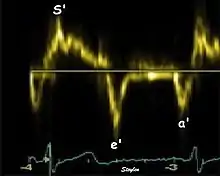

Annular velocities summarize the longitudinal contraction of the ventricle during systole, and elongation during diastole. Peak velocities are commonly used.

Systolic function

Peak systolic annular velocity (S') of the left ventricle is as close to a contractility measure as you can get by imaging[4] (bearing in mind that any imaging method only measures the result of fibre shortening, without measuring myocyte tension). S' has become a reliable measure of global function[5][6][7][8] It shares the advantage of annular displacement, that it is reduced also in hypertrophic hearts with small ventricles and normal ejection fraction (HFNEF), which is often seen in Hypertensive heart disease, Hypertrophic cardiomyopathy and Aortic stenosis.[9]

Diastolic function

As the ventricle relaxes, the annulus moves towards the base of the heart, signifying the volume expansion of the ventricle. The peak mitral annular velocity during early filling, e' is a measure of left ventricular diastolic function, and has been shown to be relatively independent of left ventricular filling pressure.[12][13][14] If there is impaired relaxation (Diastolic dysfunction), the e' velocity decreases. After the early relaxation, the ventricular myocardium is passive, the late velocity peak a' is a function of atrial contraction. The ratio between e' and a' is also a measure of diastolic function, in addition to the absolute values.